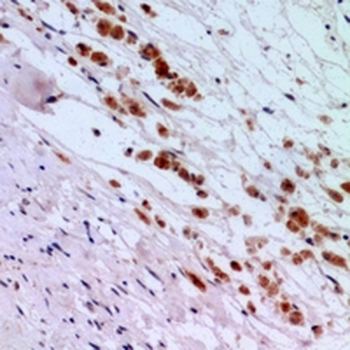

Immunohistochemical analysis of IFNAR2 staining in human brain formalin fixed paraffin embedded tissue section. The section was pre-treated using heat mediated antigen retrieval with sodium citrate buffer (pH6.0). The section was then incubated with the antibody at room temperature and detected using an HRP conjugated compact polymer system. DAB was used as the chromogen. The section was then counterstained with haematoxylin and mounted with DPX.